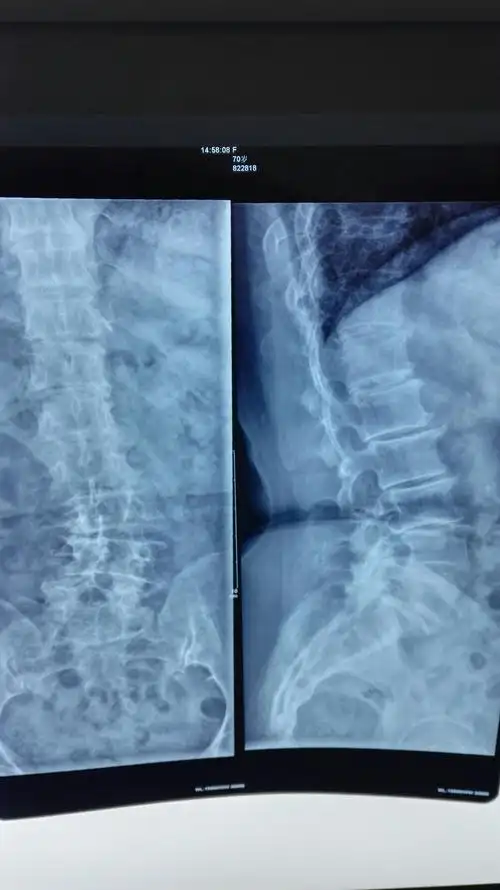

腰4/5椎间盘脱出高度向上游离病例分享——洛南县中医院骨科(副本)

典型案例二:男,48岁,腰椎间盘突出.